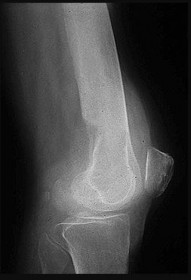

Figures 6a through 6d are the radiographs and T1-weighted sagittal and fat-saturated axial MR images of an otherwise healthy 56-year-old man who has anterior knee pain and intermittent swelling after sustaining a noncontact twisting injury. Low-power and high-power hematoxylin and eosin stained histologic specimens are shown in Figures 6e and 6f. Based on the history, radiographs, CT scan, MR imaging, and histologic findings, what is the most likely diagnosis?

The lesion in the posterior intercondylar knee notch is a benign synovial hemangioma. Intralesional calcifications, classically associated with hemangiomas, are frequently not identified on plain radiographs. The MR imaging reveals a hypervascular lesion with multiple filling defects, with hyperintensity on T2-weighted images and low-to-intermediate signal intensity on T1-weighted images. Histologically, vascular lakes within fine capillaries with a synovium on the surface of the lesion are characteristic of this condition. Many patients with synovial hemangioma have pain, swelling, stiffness, or mechanical symptoms. The correlation of symptoms with the hemangioma for this patient is unclear because there was recent trauma and a concurrent meniscus tear. Simultaneous treatment of both potential sources of pain is typically recommended. As with PVNS, the disease can be localized or diffuse. Surgical excision, either open or arthroscopic, is the recommended treatment. PVNS is the most common intra-articular tumor, but hypointensity in either the diffuse or localized type is characteristic in both T1- and T2-weighted images. Synovial sarcoma, although often found close to a joint, is not characteristically found within a joint.